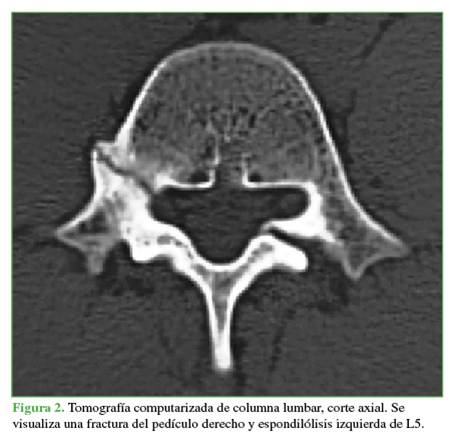

Se tomaron radiografías de columna lumbar, de frente, de perfil y oblicuas que revelaron esclerosis del pedículo derecho y espondilólisis izquierda de L5. La tomografía computarizada mostró, además de la lesión antes descrita, una solución de continuidad en el pedículo derecho, con márgenes escleróticos e hipertróficos (Figuras 1 y 2). En la resonancia magnética, se visualizó un edema en dicho pedículo lumbar (Figuras 3 y 4).

Un rasgo habitual en la pediculólisis es la esclerosis del pedículo, pero aún no resulta claro si esto representa un fenómeno de adaptación anterior a la fractura o si es una consecuencia de ella.9 Esta esclerosis unilateral le da el aspecto de vértebra anisocórica en la imagen radiológica. Sin dudas, la tomografía computarizada permite evaluar mejor el cuadro, realizar diagnósticos diferenciales, controlar la evolución y, en algunos casos, efectuar una planificación terapéutica. Las características suelen ser la presencia de solución de continuidad radiolúcida con márgenes escleróticos e hipertróficos.4 La resonancia magnética tiene una elevada sensibilidad a la hora de diagnosticar este tipo de lesiones que, si bien puede mostrar o no el trazo de fractura a nivel del pedículo, sí manifiesta el edema

como una imagen hipointensa en la secuencia T1 e hiperintensa en la secuencia T2.3,4